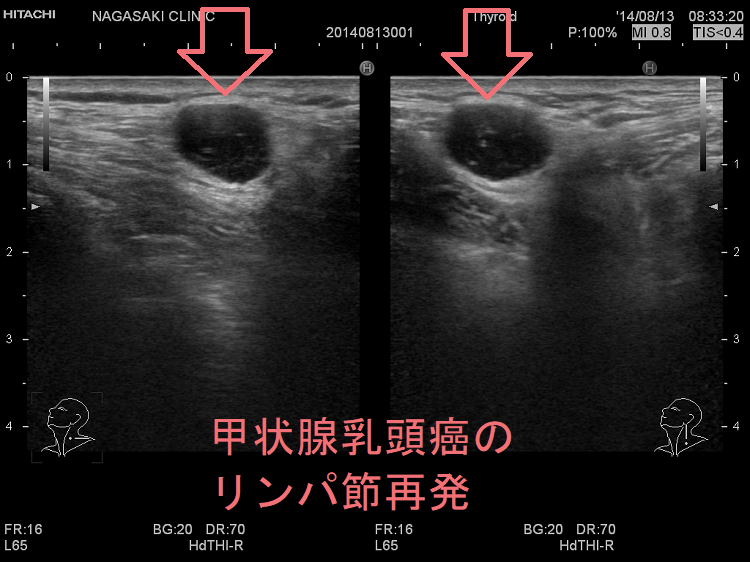

日本がん対策図鑑 | 【EGFR陽性肺がん:一次治療(PFS)】「ラズ。ZX-IPSLAP(1)|テルワールド(NTT中古ビジネスフォン販売店)。A homozygous NOTCH3 mutation p.R544C and a heterozygous。甲状腺癌腫瘍マーカー(サイログロブリン,p53抗体,SCC,CA125,CA19。。